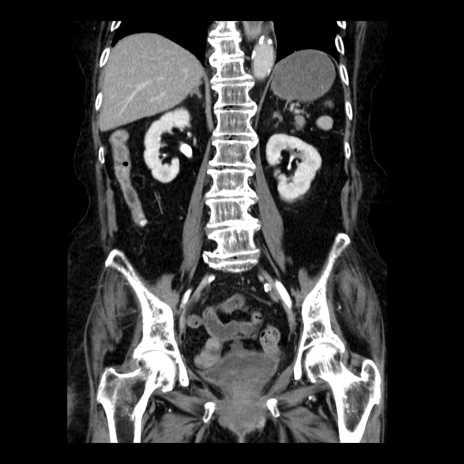

症例14(冠状断像)

【症例】 90歳代女性

【主訴】 腹痛・嘔吐

【現病歴】今朝から左側腹部痛を認めた。 経過観察していたが、嘔吐を認めたため来院。

【既往歴】 子宮癌術後

【身体所見】 意識清明、BP 127/54mmHg、P 98bpm Sp02 95%(RA)、BT 35.8°C、腹部平坦・軟腸ぜん動音聴取良好、右下腹部圧痛(+) 反跳痛なし

【データ】WBC 9800、CRP 0.46